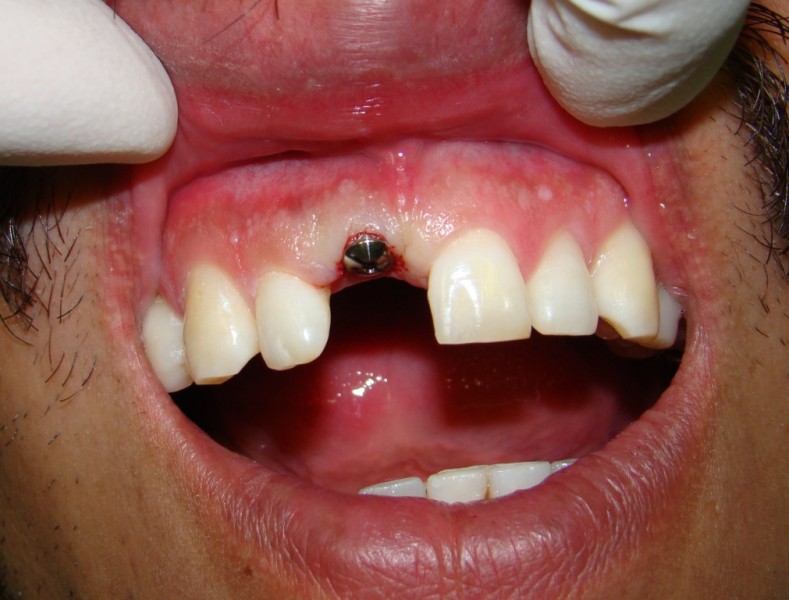

A Case with a Fractured Central Incisor